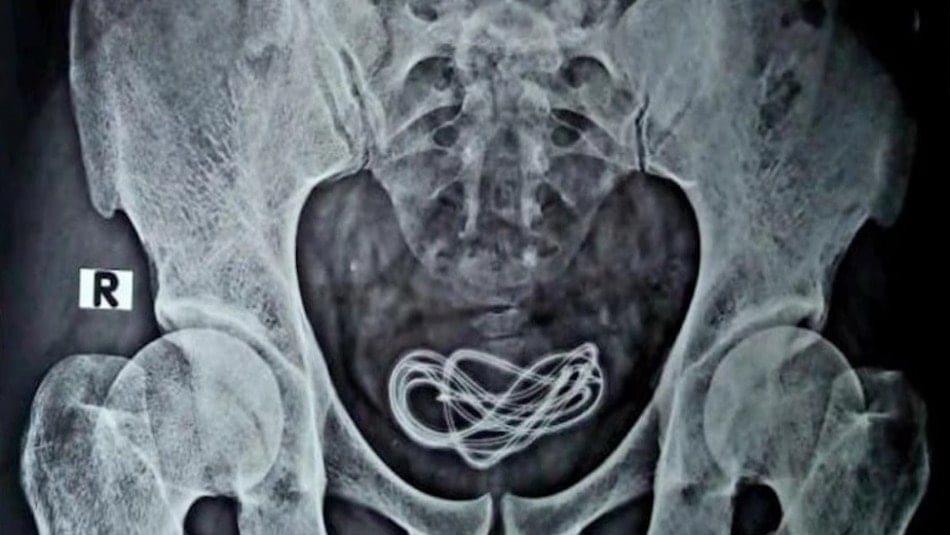

El equipo médico se dio cuenta de que el hombre se había introducido un cable de cargador de teléfono celular por el pene y terminó en su vejiga.

“Hice una incisión allí y saqué el cable, que en realidad era un cable de cargador de más de 60 centímetros de largo”, contó el cirujano.